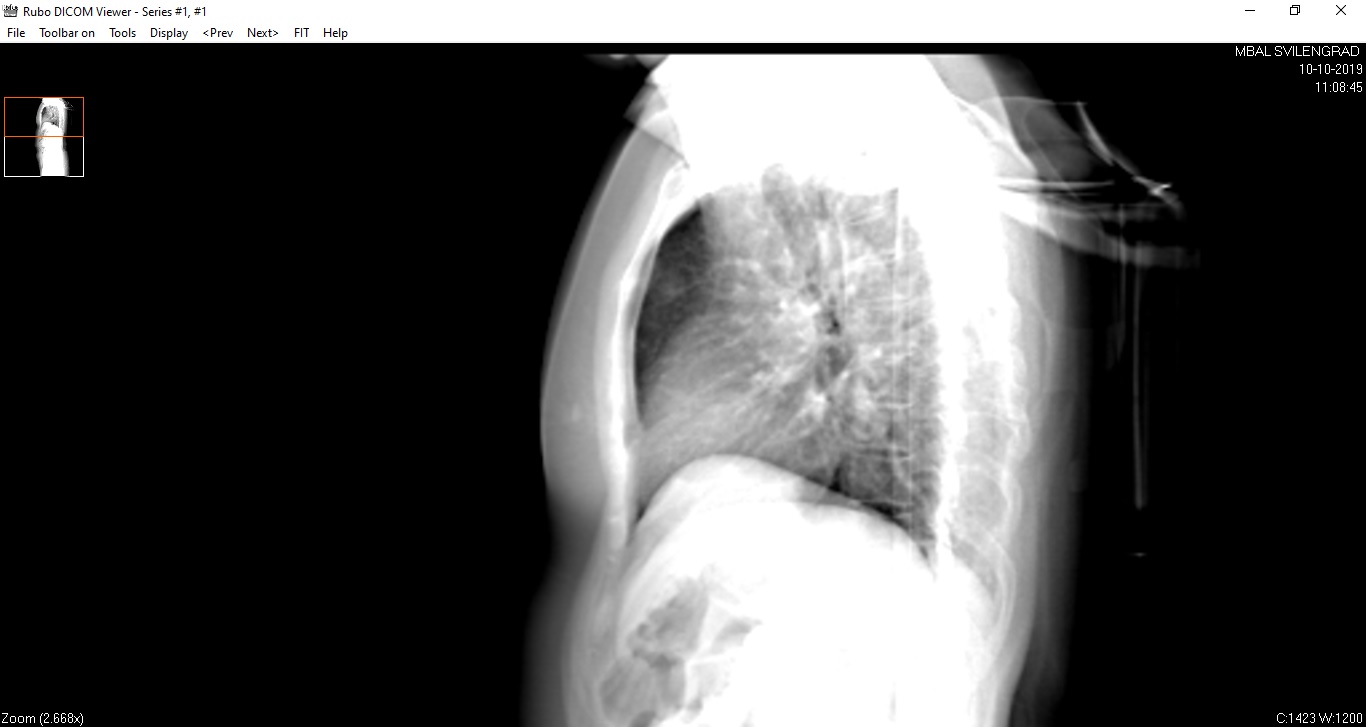

Здравейте, преди около месец на майка ми и правиха скенер на прешлени и гръбначен стълб, относно шум в ушите (който е от няколко месеа и не се повлиява от лекарства) със съмнение за ошипяване, лекарят, който е разчел резултатите от скенера и казал, че се вижда нещо на белия дроб и е добре да се обърне към пулмолог, за да и направи допълнителни изследвания. Свързахме се с лекар пулмолог, но тя не прегледа скенера, а само я прослуша и я изпрати на рентген, където не се видя нищо, което е според мен е логично, защото доколкото разбирам от скенера той е правен в профил, а рентгенографията в анфас, моля за Вашето мнение, относно снимките от скенера и тази от рентгена.

Прикачени файлове

Rentgen-MK.jpg

Rentgen-MK.jpg (148.86 KiB) Прегледано 1599 пъти

MK-skener.jpg

MK-skener.jpg (83.17 KiB) Прегледано 1599 пъти

MK-skener-2.jpg

MK-skener-2.jpg (170.46 KiB) Прегледано 1599 пъти

За коректно мнение, касаещо здравето на майка Ви, ще Ви препоръчаме отново да се обърнете към лекар-специалист. Скенерът е част от диагностичното звено. За адекватно медицинско мнение е необходимо да се представят клинични оплаквания, да се проведе физикално

изследване. Без тях интерпретацията на дадено инструментално изследване крие риск от диагностични грешка.